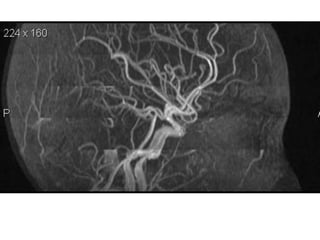

Arteries of the brain (lateral view) - MRA

1. Anterior cerebral artery

2. Anterior communicating artery

3. Basilar artery

4. branches (in insula) of middle cerebral artery

5. Cavernous portion of internal carotid artery

6. Cervical portion of internal carotid artery

7. Genu of middle cerebral artery

8. Intracranial (supraclinoid) internal carotid artery

9. Middle cerebral artery

10. Ophthalmic artery

11. Petrous portion of internal carotid artery

12. Posterior cerebral artery

13. Posterior cerebral artery in ambient cistern

14. posterior cerebral artery in interpeduncular

cistern

15. Posterior communicating artery

16. Posterior inf cerebellar artery.

17. Quadrigeminal portion of posterior cerebral

artery

18. Superior cerebellar artery

19. Vertebral artery